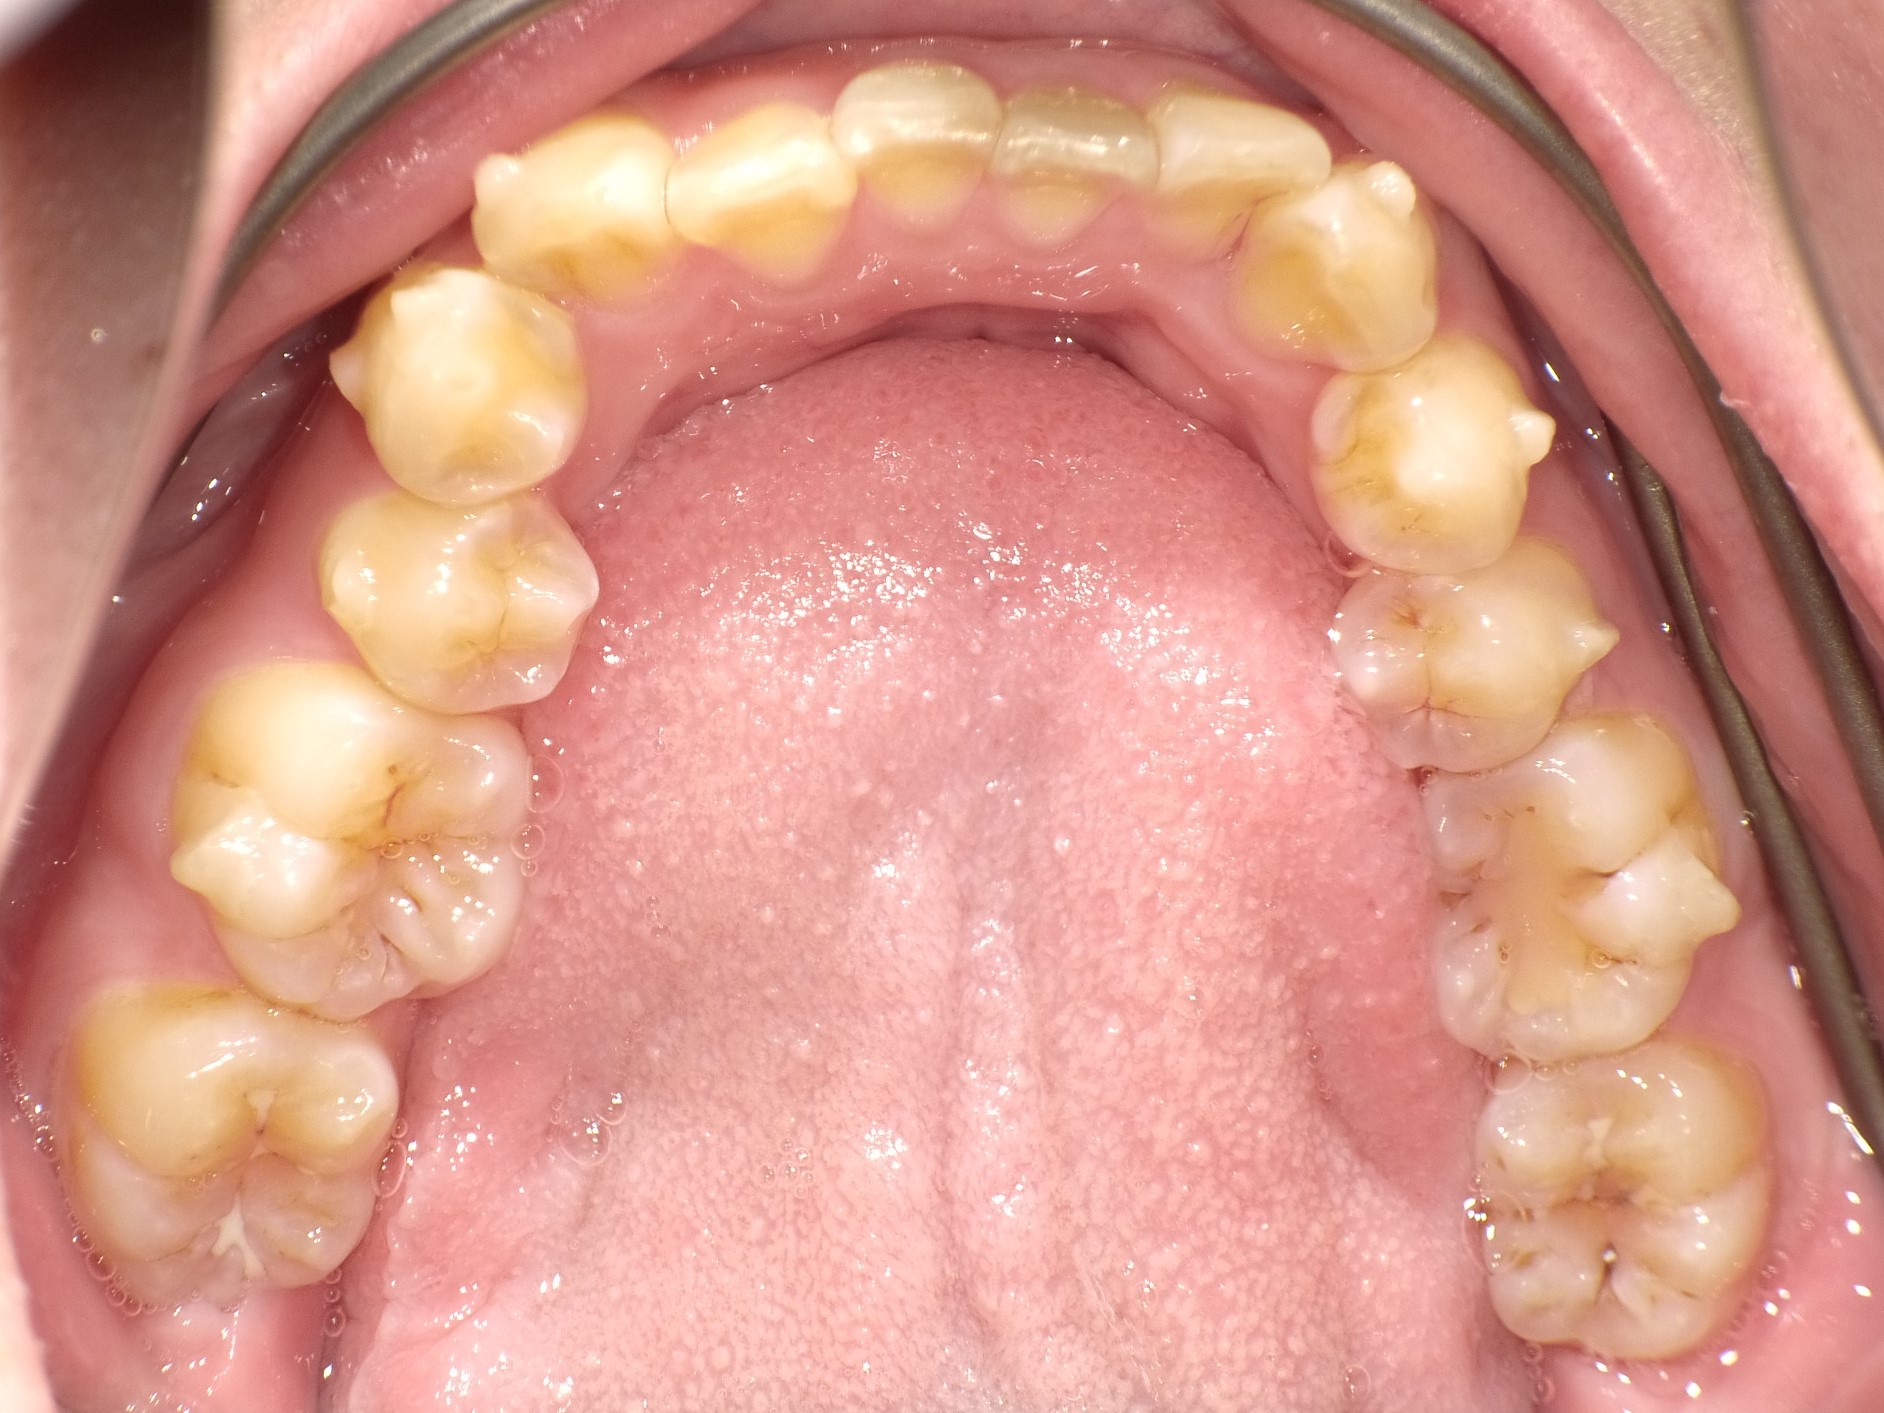

インビザライン(マウスピース矯正)治療中の方の写真になります(^^)

下の写真見比べていただくとわかると思うのですが前歯が綺麗に並び始めてきました☆